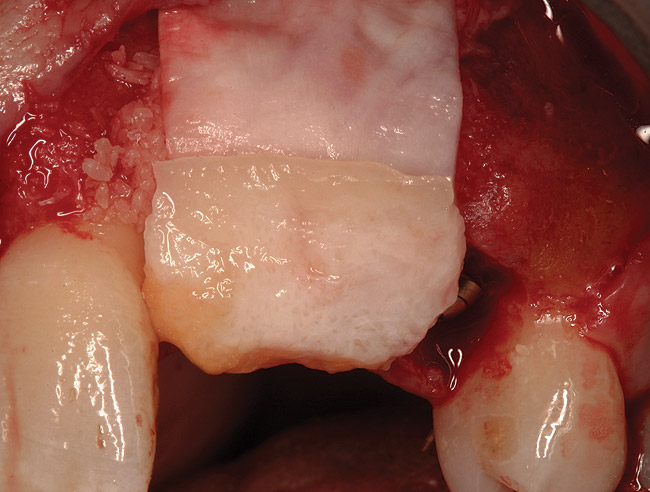

Figure 17  (Case 2) Long-term resorbable membrane in place with autogenous connective tissue.

Figure 17